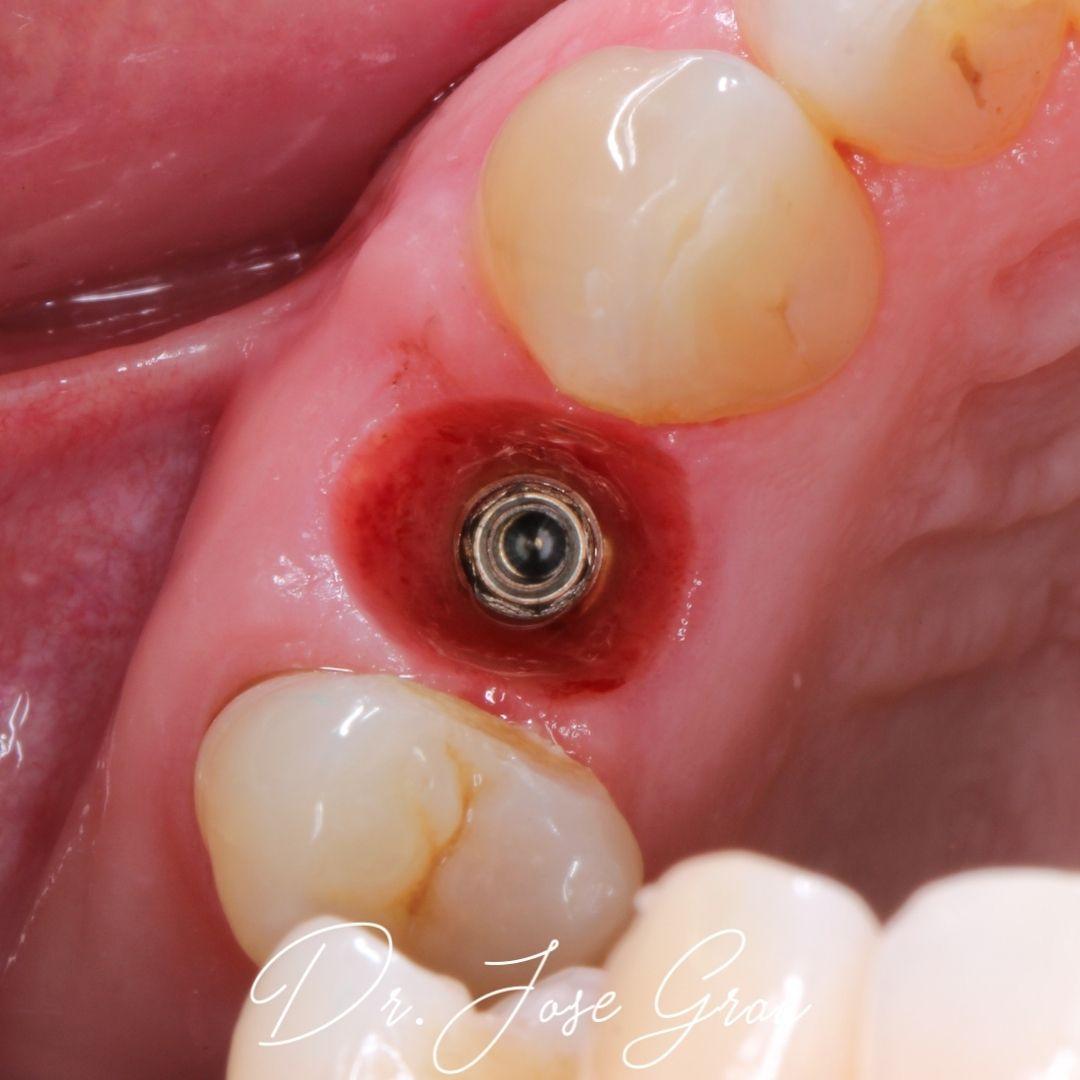

Manejo área estética con implantología inmediata